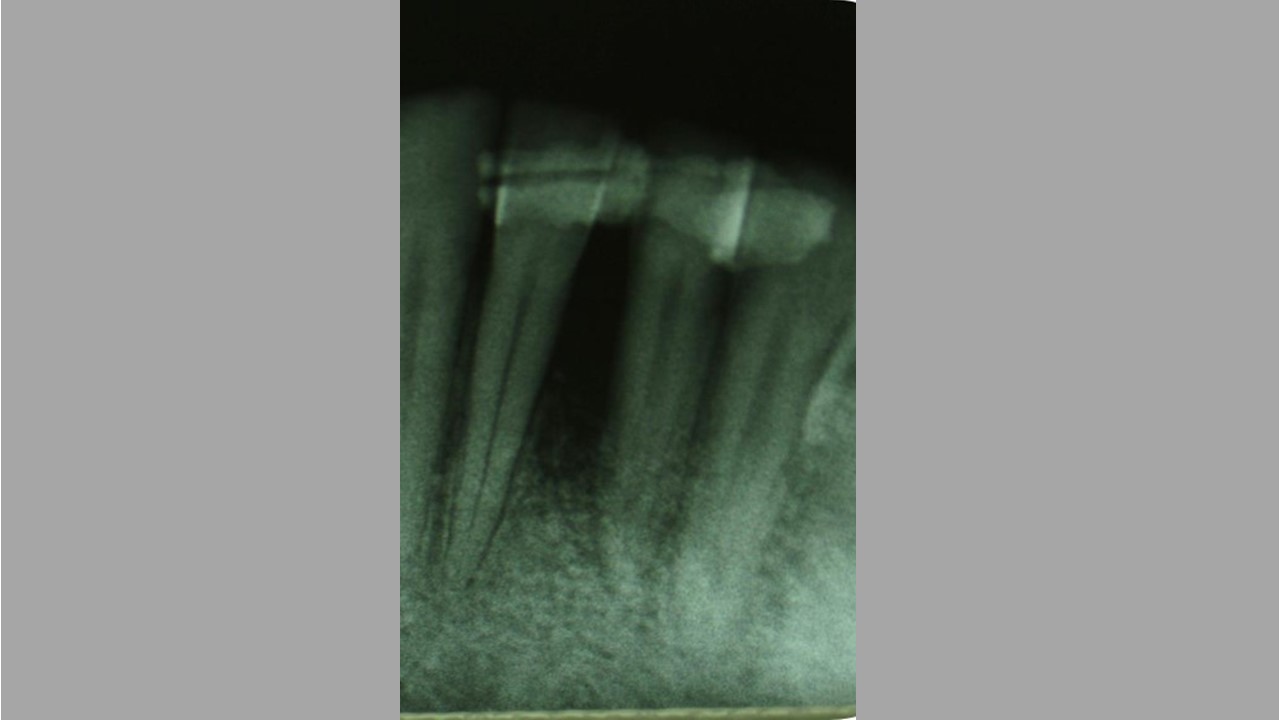

02/12 - Pre-operative radiograph. Deep intrabony defect at tooth 31.Two-wall intrabony defect treated using cerabone® and Straumann® Emdogain® - Dr. D. Rakasevic & Prof. Dr. S. Jankovic